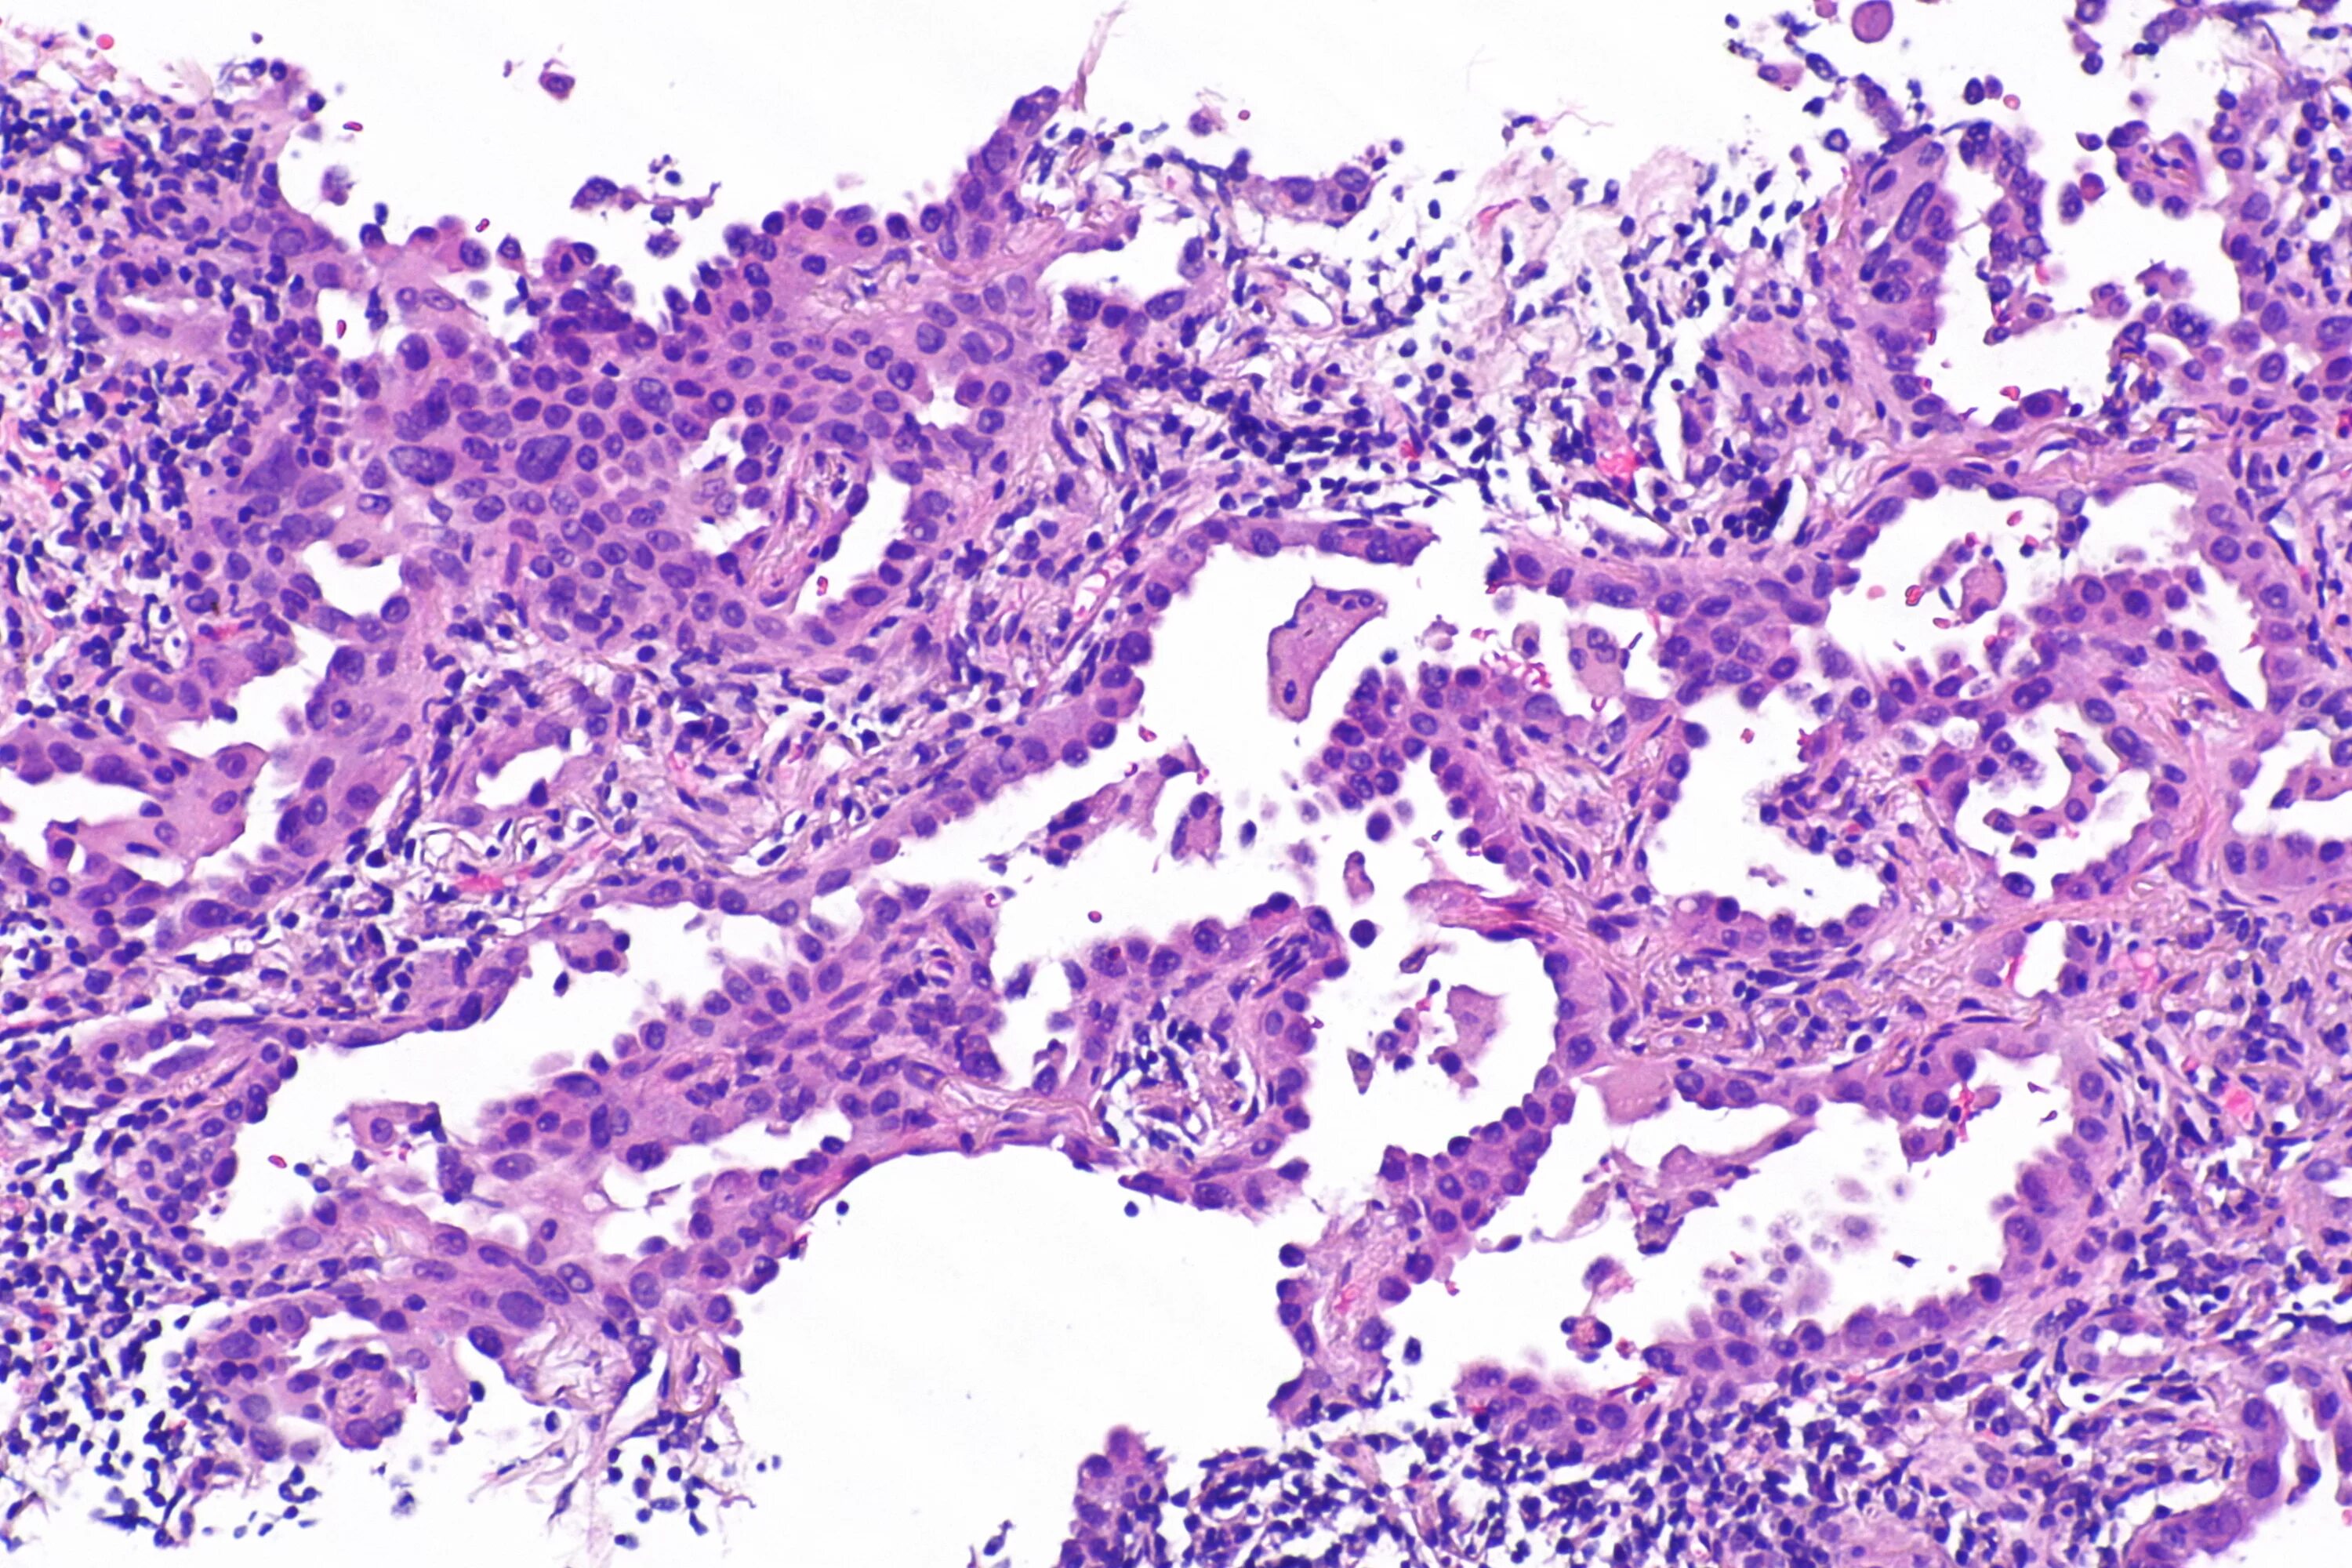

Аденокарцинома легких 4 стадия прогноз